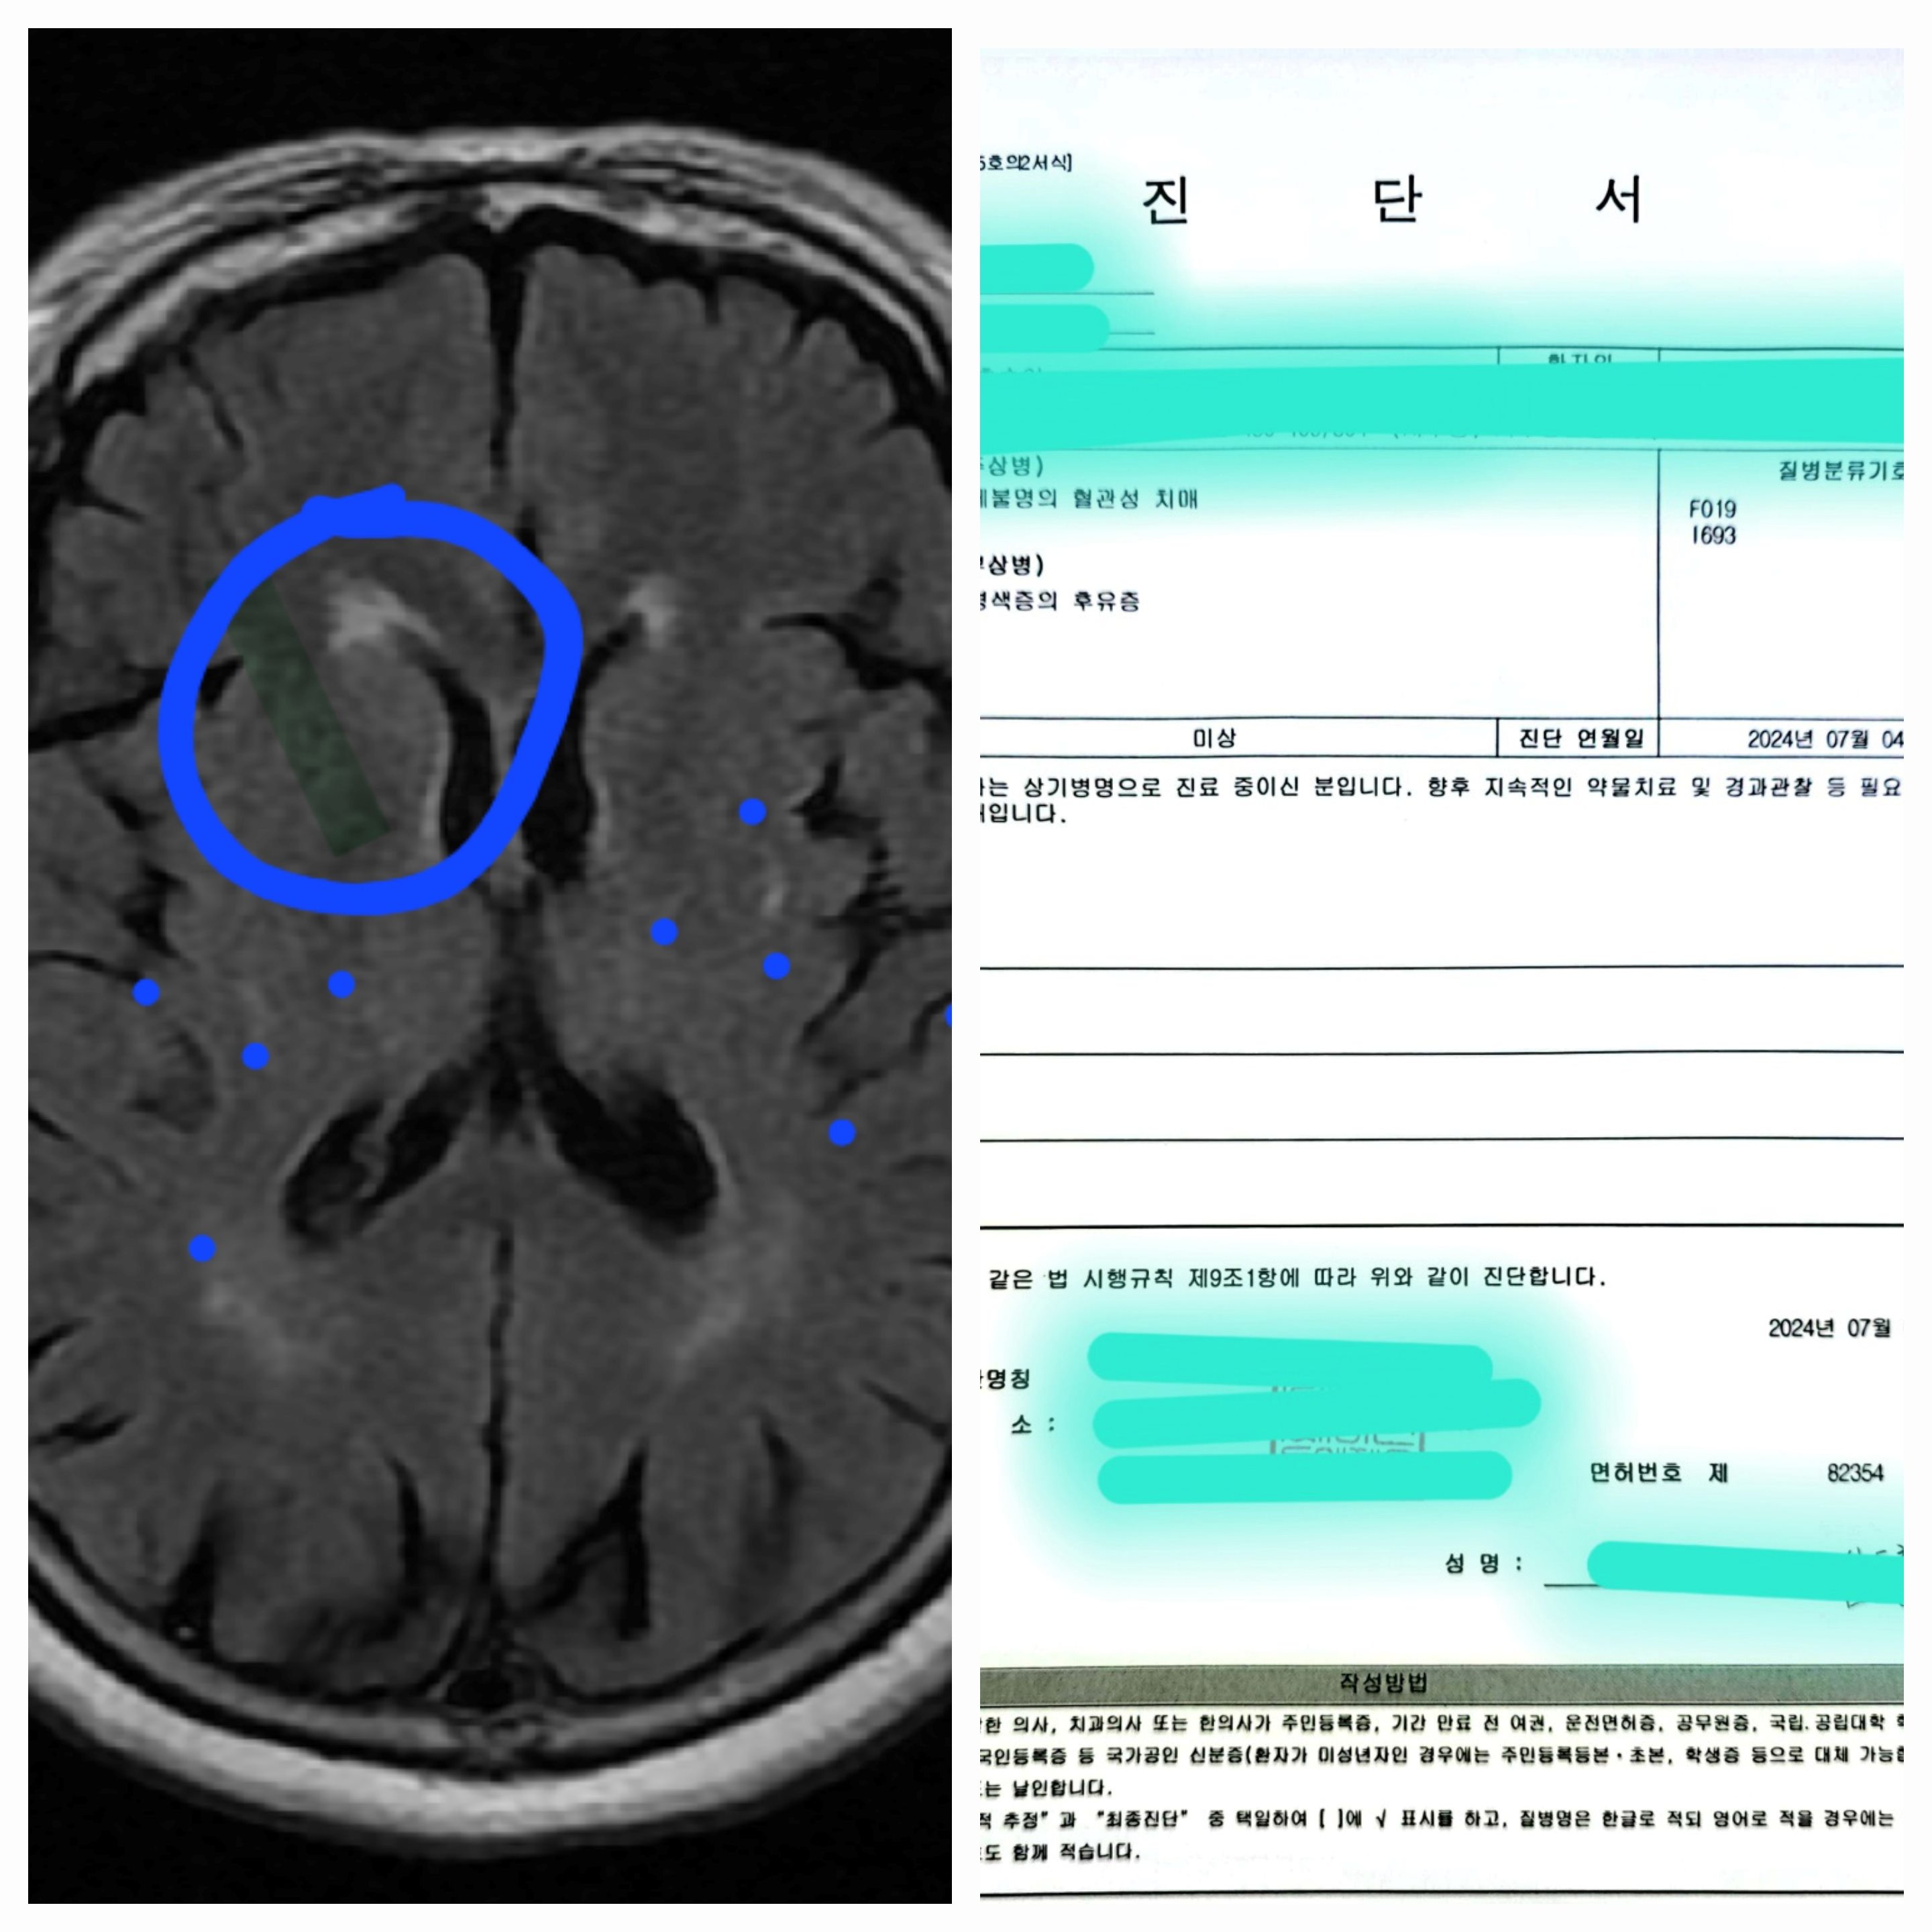

- 진단 결과: 상세 불명의 혈관성 치매, 뇌경색증의 후유증

- 운동 및 감각을 관장하는 부위에 뇌경색이 발생했음

- 군데군데 미세출혈 등의 뇌출혈도 있었음

- 혈관성 치매는 뇌졸중으로 인한 뇌 손상으로 발생하는 치매 유형입니다.

요약하면, 어머님은 뇌경색과 뇌출혈로 인한 혈관성 치매 진단을 받았습니다. 지속적인 약물 치료와 경과 관찰이 필요하며, 뇌졸중 예방과 관리가 중요할 것으로 보입니다. 치매 극복을 위해 전문의와 긴밀히 협력하여 체계적인 관리가 필요할 것 같습니다.